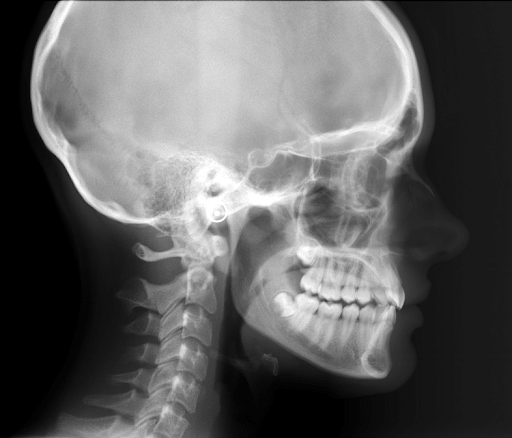

With Cephalomatric radiograph we can assess the inclination of teeth for orthodontic treatment.

Cephalomatric Radiograph